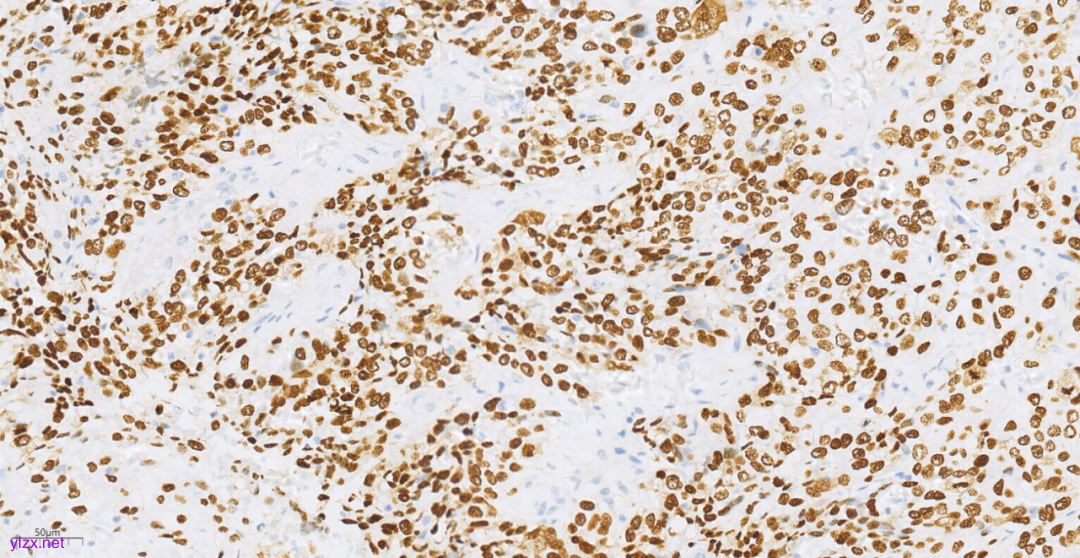

3.3免疫组化(图10-图12):

鳞癌成分CK(+),P40(+),CK5/6(+),p63(+),CK7(-),CK20(-),ER(-),PR(-),WT-1(-),Ki-67(约70%+).

图10 免疫组化示肿瘤细胞P40(+)。

图11 免疫组化示肿瘤细胞CK5/6(+)。

图12 免疫组化示肿瘤细胞p63(+)。